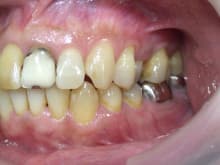

上顎前歯のセラミック治療の症例をご紹介します。

上の前歯は

不適合な被せ物や詰め物がしてありました。

もともと神経の処置もしてあった歯ですが

2次虫歯や根尖病巣(根の先の病気)があったため

顕微鏡下での専門根管治療等も行っています。

セラミックでの被せ物治療を希望していたので